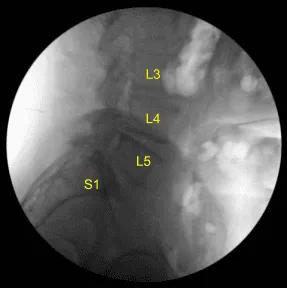

He was positioned prone on a Jackson Relton-Hall frame. All pressure points were carefully padded. They received preoperative prophylactic IV antibiotics, tranexamic acid and dexamethasone. Lumbar area was prepped with an electric hair clipper and cleaned with chlorhexidine. A 23-gauge spinal needle and fluoroscopy was used to localize the index level.

The C-arm unit, which was draped sterilely, was brought into the field and used to confirm the level. Neuronavigation array was affixed to the right superior posterior iliac crest with two Schanz pins after infiltrating with local anesthesia and making #15 blade stab incisions.

The patient was sterilely draped. CT scan was obtained. Data was transferred to the neuronavigation computer. Accuracy was verified. Neuronavigation techniques were used to morselized bone for arthrodesis autograft. Leksell rongeurs, Kerrison rongeurs and electric high-speed drill under continuous sterile irrigation were used to perform complete L4-5 laminectomy and facetectomies, completely neurolyzing with Penfield-Metzenbaum technique the L4, L5 and S1 nerve roots.